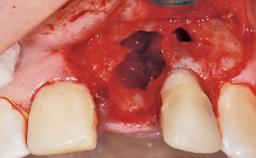

Late Flapless Placement of an Implant in a Maxillary Left Central Incisor Site

A 39-year-old male patient presented with a chief complaint of discomfort and gingival discoloration around his maxillary left central incisor. He was in good general health and was a non-smoker. His past dental history was significant because of the traumatic fracture of tooth 21 in a sporting accident at age 13. Initial dental treatment included endodontic therapy and a full-coverage restoration. The patient became symptomatic 5 years later, when structural failure of the tooth resulted in the dislodgment of the crown. Endodontic retreatment, apical surgery, and post-and-core restoration were performed.

Bone Volume Horizontally and vertically sufficient Horizontally deficient Deficient vertically or deficient vertically AND horizontally

Bone Volume Deficient horizontally, requiring prior grafting